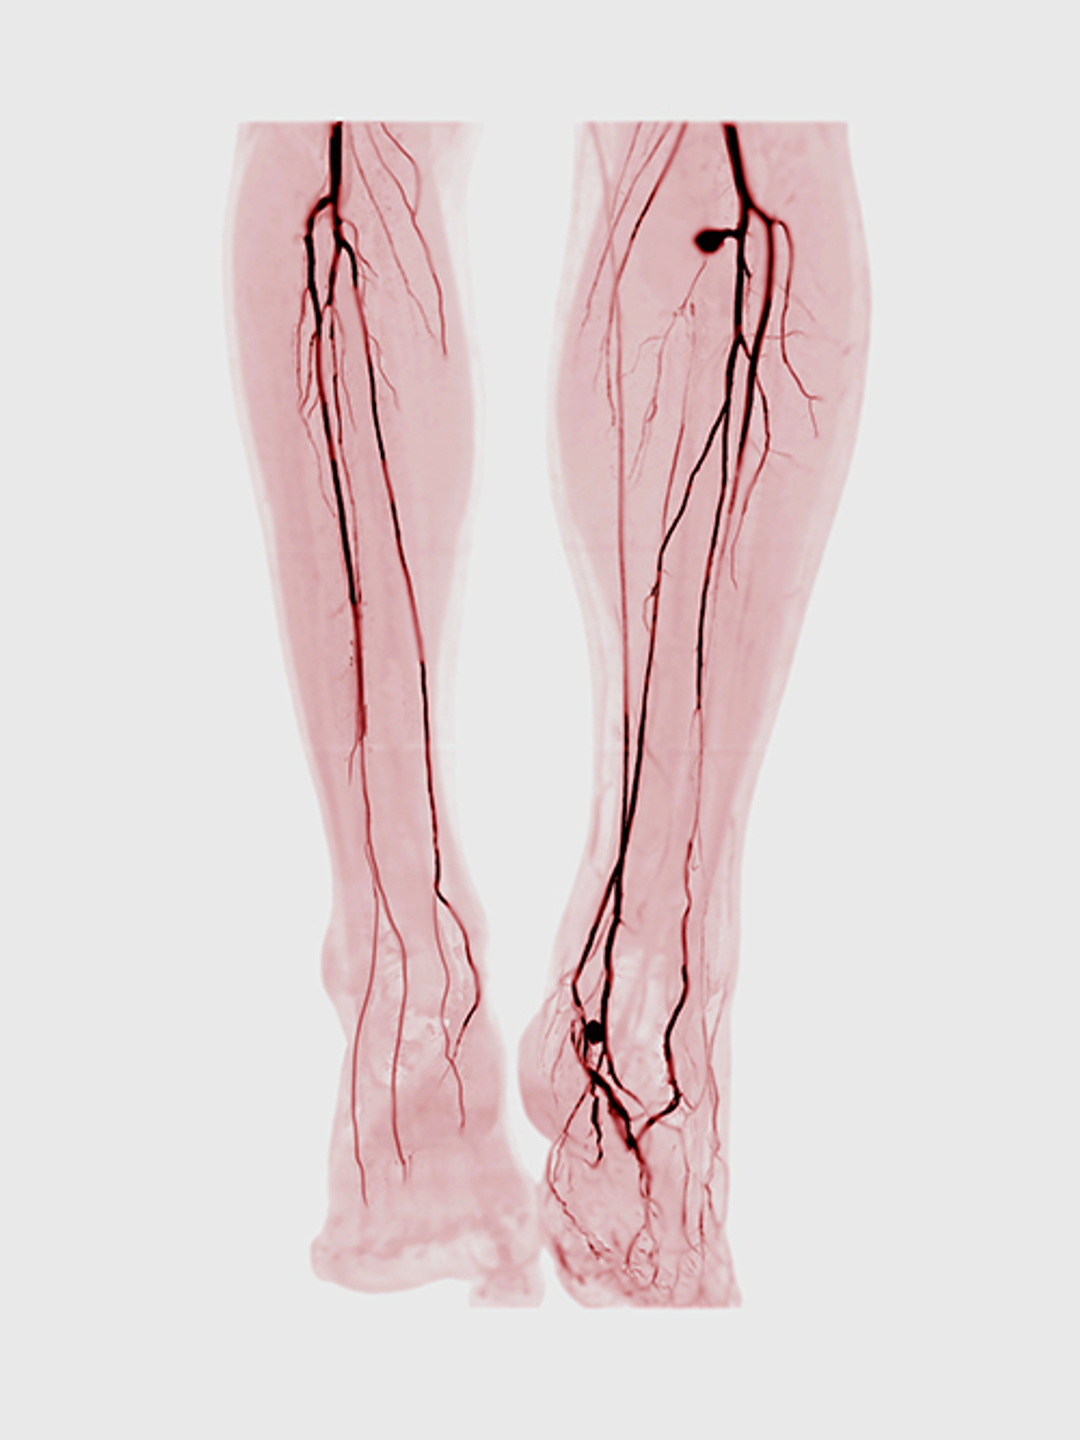

An angiogram of the legs is shown, demonstrating blockages in multiple arteries

A condition for which leg pain (claudication) is the chief symptom, PAD has a significant effect on function and quality of life. The disease involves vascular stenosis and ischemia in the calves and feet as a result of occlusive atherosclerosis of the aorto-iliac, femoropopliteal, and infra-popliteal arteries. Beyond pain, early symptoms include cramping, paresthesias, and cold feet.